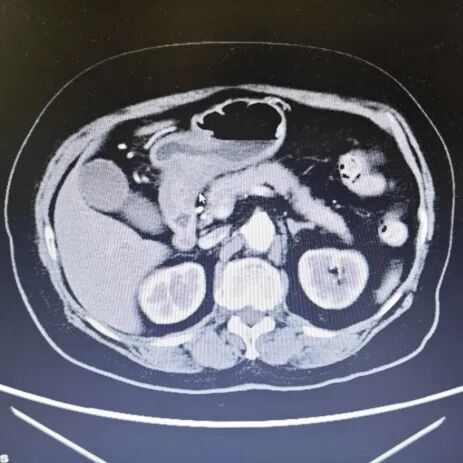

内容提要 近日,在葫芦岛市第二人民医院胃肠外科主任、原锦州医科大学附属医院胃肠外科主任乔世峰教授主刀下,成功为一位73岁的高龄胃癌患者实施了高难度胃远端切除术伴胃-十二指肠吻合术(毕Ⅰ式),充分彰显了乔世峰主任在胃肠道肿瘤外科领域深厚的技术功底与丰富经验。 1 高难手术,助力快速康复 李奶奶今年3月在外院被确诊为(胃窦-胃角)恶性肿瘤,辗转到我院寻求进一步手术治疗。考虑到患者年龄较大、病灶位置复杂,乔世峰主任在术前全面评估后,决定采用胃远端切除术伴胃-十二指肠吻合术。 肠镜及病理结果 该术式属于四级手术,技术要求高,但对患者术后生活质量有明显优势:在完整切除肿瘤、系统清扫周边淋巴结的同时,保留十二指肠原有生理位置,行胃后壁与十二指肠端侧吻合(毕Ⅰ式),吻合后更符合人体正常消化通路,术后并发症少,恢复更快。 乔世峰主任凭借40余年胃肠外科临床经验,携张凯副主任及团队成员,从容完成肿瘤完整切除及淋巴结清扫,确保根治效果。随后,精准实施胃后壁与十二指肠端侧吻合,吻合通畅、血供良好,整个手术过程平稳。术后患者消化功能恢复快,并发症发生率显著降低,生活质量更高。 胃部影像(鼠标所指为病变处) 此次高难度手术的成功实施,再次体现了我院在复杂胃肠外科治疗中的技术实力。乔世峰教授深耕临床多年,在胃肠道肿瘤的规范化治疗及疑难病例诊疗等方面有着深厚的造诣和丰富的临床经验,尤其擅长各类腹腔镜胃肠肿瘤根治术,致力于为患者提供创伤更小、恢复更快、根治更彻底的诊疗服务。 随着乔世峰教授的加盟,我院胃肠外科的学科建设和诊疗能力迈上了新台阶。未来,科室将在乔世峰主任的带领下,持续深耕技术创新,不断优化诊疗服务,全力提升胃肠道肿瘤及疑难重症的诊治水平。 2 人民医院 人民名医 乔世峰 博士后 主任医师 教授 硕士研究生导师 ·葫芦岛市第二人民医院胃肠外科主任 ·原锦州医科大学附属第一医院胃肠外科主任 ·首都医科大学医学博士、天津医科大学博士后 ·辽宁省医学会外科分会疝与腹壁外科学组委员 ·辽宁省医学会肠外肠内营养学会委员 ·东北三省肠外肠内营养支持专业委员会委员 ·辽宁省中西医结合学会肿瘤专业委员会常委 ·《中国肿瘤生物治疗杂志》特约审稿专家 专业特色:省内胃肠外科领域领军专家,从事普外科工作近40年,擅长胃肠道多发、疑难病诊治,精通普外科各类手术,如胃癌、结肠癌、疝、肠梗阻、肝癌、胆囊切除术、胰腺手术等。深耕胃肠道肿瘤规范化治疗与微创技术创新,在省内较早开展腹腔镜微创胃肠肿瘤手术,具有极高造诣。在国家核心期刊发表学术论文20余篇,SCI论文10余篇。 出诊时间:每周三全天 咨询热线:0429-8010259 张凯 副主任医师 硕士研究生 ·葫芦岛市第二人民医院胃肠外科副主任 ·辽宁省生命科学学会胃肠肿瘤专业委员会委员 ·中医临床药学分会委员理事 ·沈阳市抗癌协胃癌专业委员会委员 专业特色:以腹部外科为诊治方向,擅长普通外科多发及疑难病的诊断、治疗和手术。以微创技术为特色优势,擅长腹腔镜阑尾切除术、腹股沟疝修补术、结直肠癌根治术、胃癌根治术。先后发表论文2篇,完成“腹腔镜、胆道镜及两镜联合手术临床应用”科研项目,并获得了葫芦岛市科学技术成果奖励二等奖,学术论文类获得葫芦岛市自然科学学术成果一等奖。